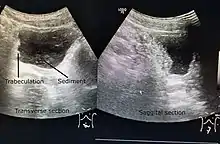

Ultrasound imaging can give information on the shape of the bladder, post-void residual volume, and evidence of kidney damage such as kidney size, thickness or ureteral dilation.[5] Trabeculated bladder on ultrasound indicates high risk of developing urinary tract abnormalities such as hydronephrosis and stones.[6] A voiding cystourethrography study uses contrast dye to obtain images of the bladder both when it is full and after urination which can show changes in bladder shape consistent with neurogenic bladder.[5]